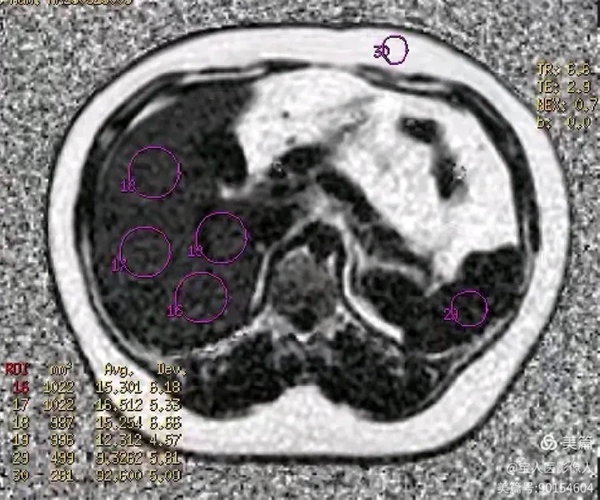

圖6

PDFF測值,測量全肝實質(zhì)多部位的脂肪分?jǐn)?shù)值12%—17%,提示:脂肪肝,MR-PDFF,二級,中度。